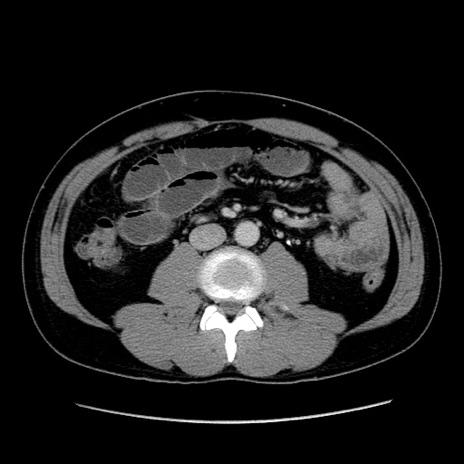

冠状断像

【症例】30歳代男性

【主訴】腹痛、嘔吐

【現病歴】昨晩から突然の腹痛あり、その後嘔吐、軟便も出現。腹痛が改善しないため救急搬送となる。2日前にしめ鯖の食事歴あり。

【身体所見】意識清明、苦悶様、BP 135/90mmHg、BT 35.7℃、腹部:平坦、やや硬、心窩部〜臍部に自発痛、圧痛あり、筋性防御+、反跳痛-

【データ】WBC 8100、CRP 0.57